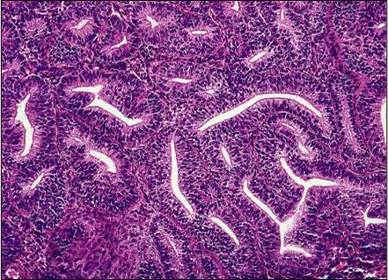

Diagnóstico e micro. Hiperplasia Endometrial Complexa de Baixo Grau. Glândulas proliferadas, tortuosas, irregulares e justapostas sem atipias.

Hiperplasia Endometrial Complexa de Alto Grau.